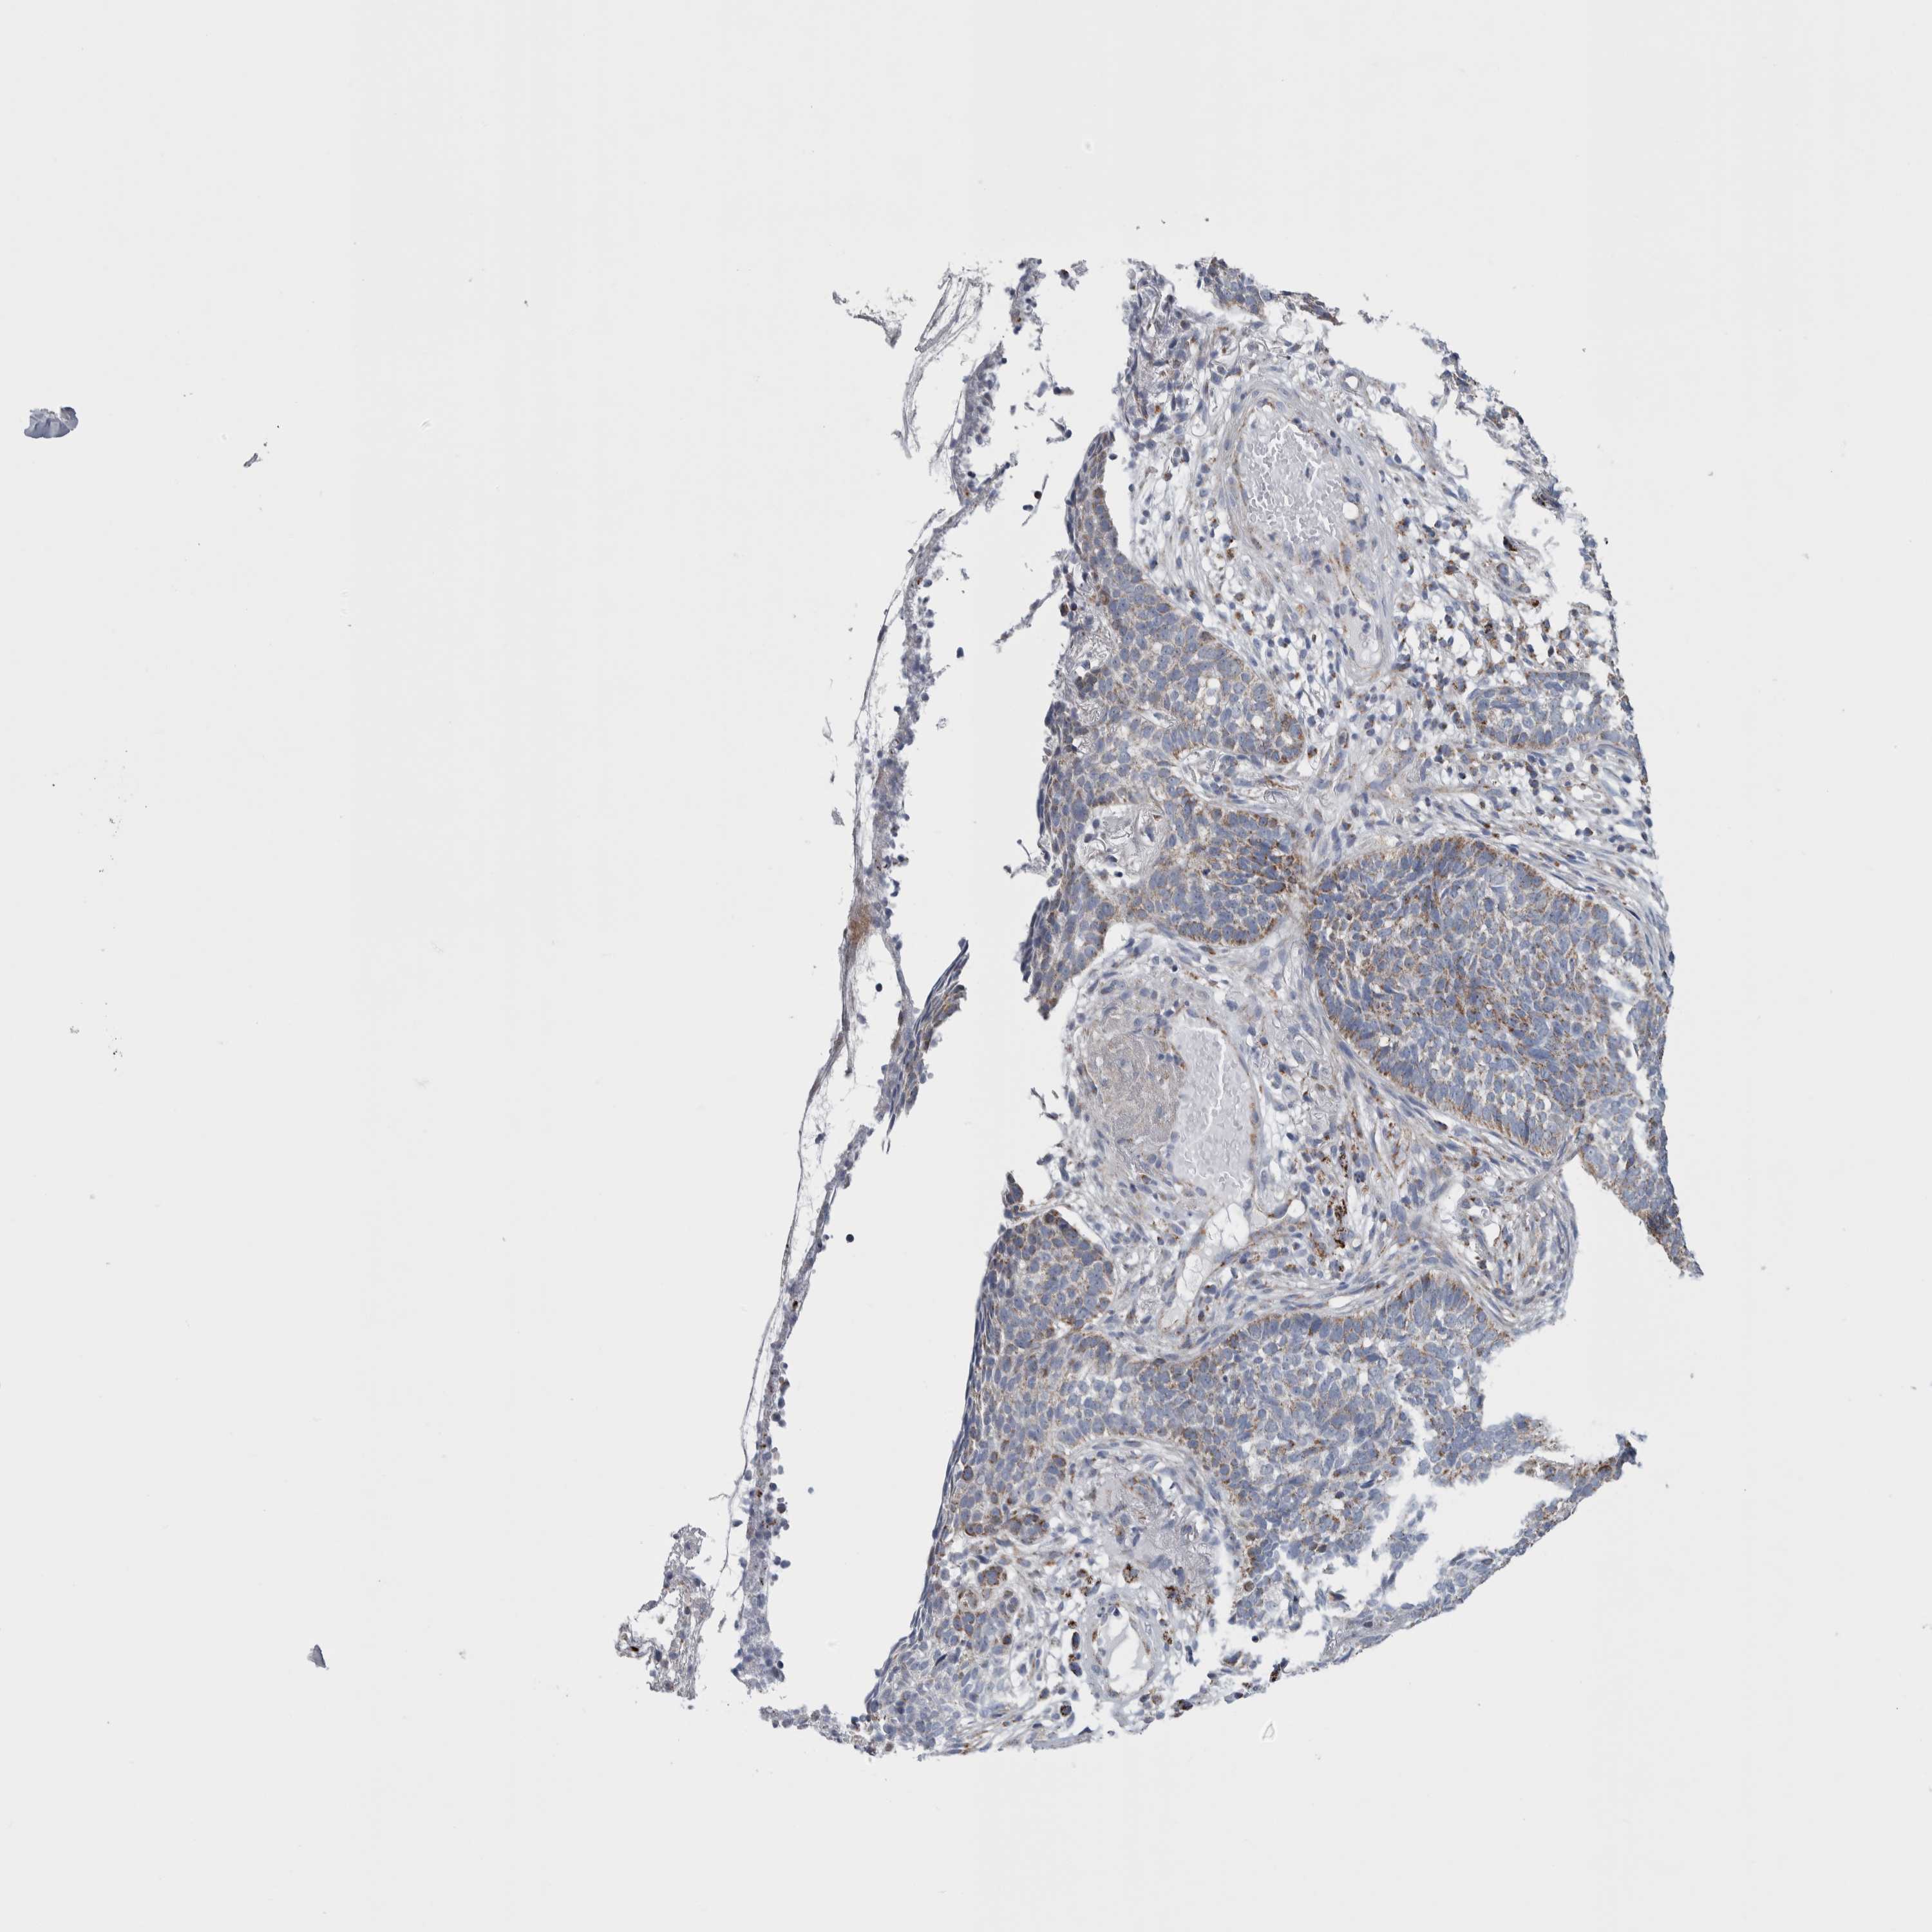

SKIN CANCER - Protein expressioni

A mouse-over function shows sample information and annotation data. Click on an image to view it in a full screen mode. Samples can be filtered based on level of antibody staining by selecting one or several of the following categories: high, medium, low and not detected. The assay and annotation is described here.

Each image is clickable and will lead to virtual microscopy that enables deeper exploration of all samples and also displays staining intensity scores, fraction scores and subcellular localization as well as patient and tissue information for each sample.

Antibody HPA018996

Squamous cell carcinoma, metastatic, NOS